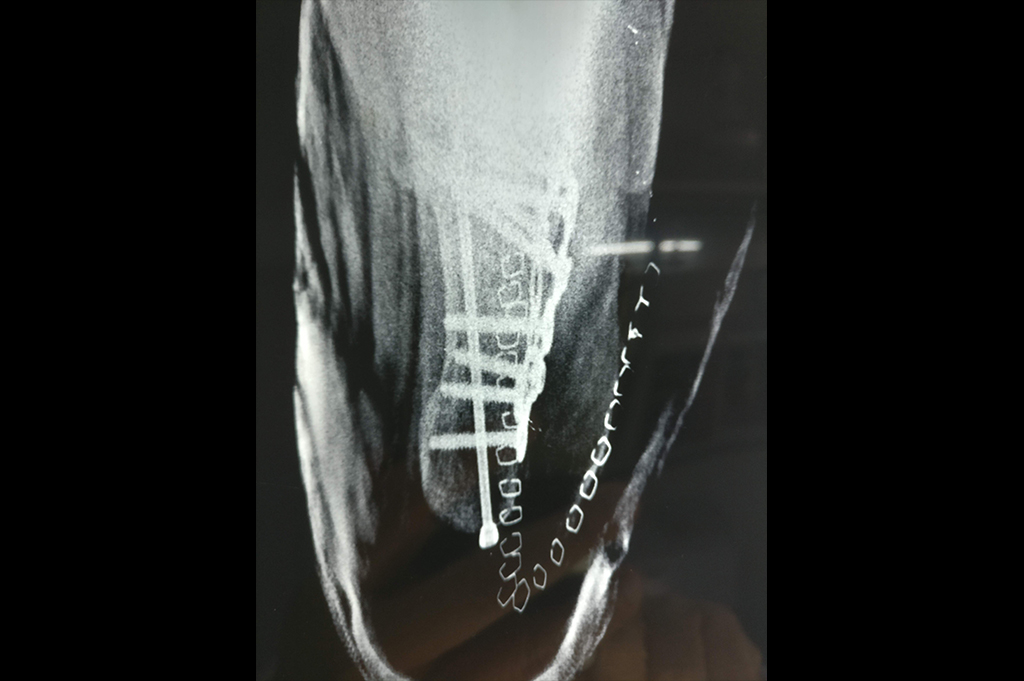

Calcaneum